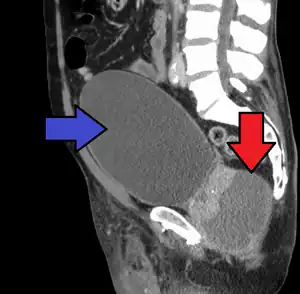

People who are severely ill may need hospitalization, while others can be treated at home with bed rest, analgesics, stool softeners, and hydration. Men with acute prostatitis complicated by urinary retention are best managed with a suprapubic catheter or intermittent catheterization. Lack of response to antibiotics should raise the suspicion of an prostate abscess and prompt an imaging study such as a transrectal ultrasound (TRUS).[10]